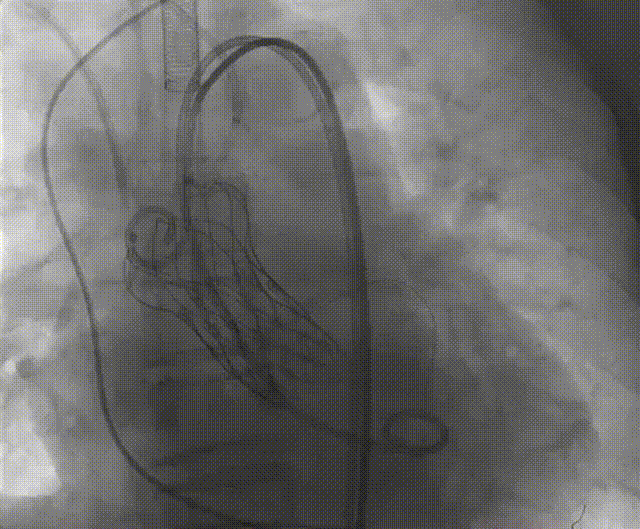

手术流程概括

零位定位开始释放,一次释放,零位释放位置良好,决定完全释放。

释放后多体位观察造影,瓣膜位置良好,展开良好,轻微瓣周漏。